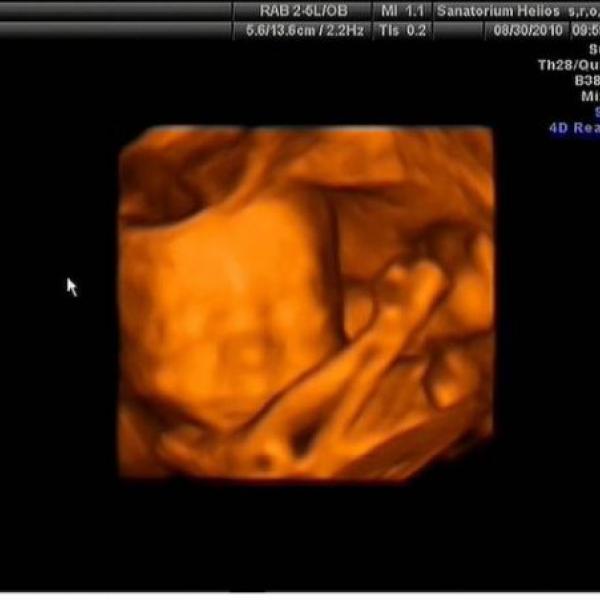

Ahoj spolutěhulinky :) tak jsem konečně taky vyfotila domeček našeho Tobíka :h: je to focené před týdnem v 30tt a už teď mi přijde, že mám pupík zase větší :00: Večer už mi vad